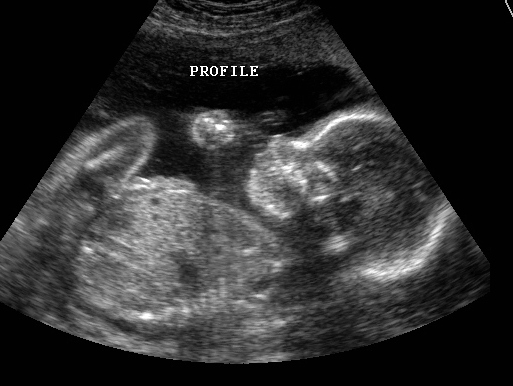

It's a . . .

GIRL!!!!!!!!!!! I am so excited I can barely stand it. We went in for my ultra sound today and everything went just as we had hoped. The doctor checked all the vitals and said that everything looked perfect. 10 fingers, 10 toes, and much to my relief, no cleft lip and/or pallet. Then at the very end, he confirmed that, yes, this sweet new little thing was in fact a girl. He checked every nook and cranny that he could see to make sure that nothing was hiding :) I knew there was another girl that needed to come to our wonderful family. Lloyd informed me that this was my last shot at getting her before I had to find myself another donor :)